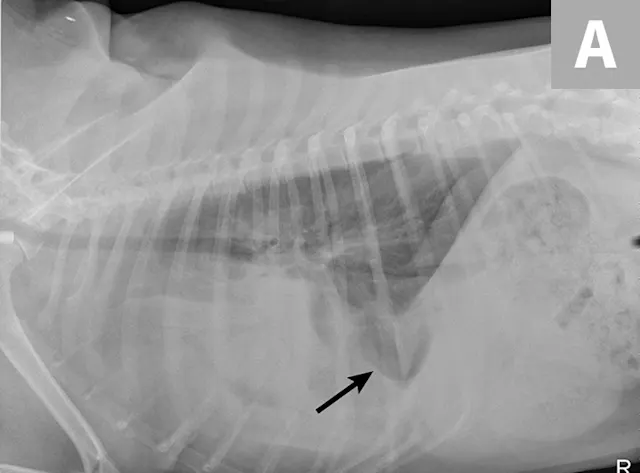

Right lateral thoracic radiographs revealed a large amount of fluid/soft tissue opacity obscuring the cardiac silhouette. Ventrodorsal radiographs showed increased soft tissue opacity in the left hemithorax, primarily in the cranial and middle lung fields. A mild interstitial pattern, a pleural fissure line, and border effacement of the heart were noted in the left hemithorax (Figure 1).

FIGURE 1A

Right lateral (A) and ventrodorsal (B) thoracic radiographs obtained prior to thoracocentesis demonstrating a mild interstitial pattern, moderate pleural effusion, soft tissue opacity in the left cranial and middle lung field, border effacement of the heart, and a pleural fissure line (arrows)

Radiography findings suggested a combination of pulmonary and pleural space disease. Differential diagnoses included pleural effusion (eg, hemothorax, pyothorax, chylothorax, hydrothorax, neoplasia) and pleural space mass or mass effect (eg, neoplasia, lung lobe consolidation or torsion, abscess/granuloma).